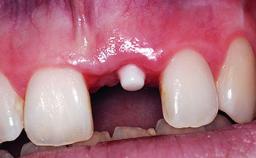

Replacement of an Ankylosed Upper Left Central Incisor: Bone Augmentation and Socket Grafting, Late Placement of an RC Bone Level Implant

# of Implants 1

Type of Implants Two-Piece

Placement Protocol Early or late implant placement

Bone Volume Deficient horizontally, requiring prior grafting